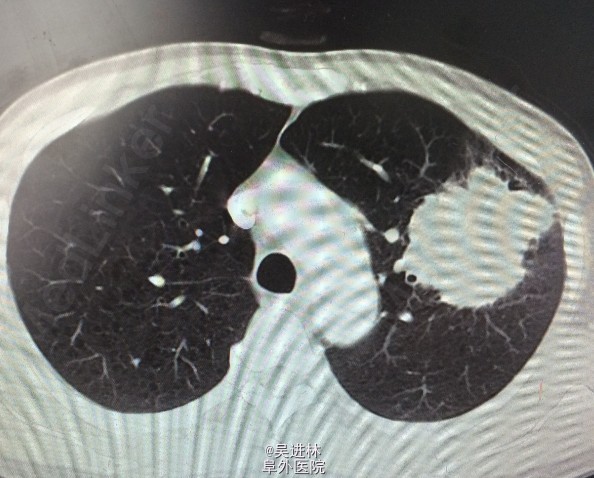

患者男,58岁,主因“咳嗽,体检发现肺部占位5个月。患者5月前无明显诱因出现咳嗽,以夜间为重,遂至外院就诊,行胸部CT检查提示左肺下叶肺不张,伴胸腔积液,纵隔淋巴结轻度肿大;行气管镜检查并取组织病理活检提示为肺鳞状细胞癌。已在我院予以多西他赛+氨磷汀化疗方案治疗,治疗期间未见明显不良反应。患者自发病来,近5个月来体重下降8Kg。

CT:左肺巨大肺癌

诊断:左肺鳞癌 处理:左全肺切除